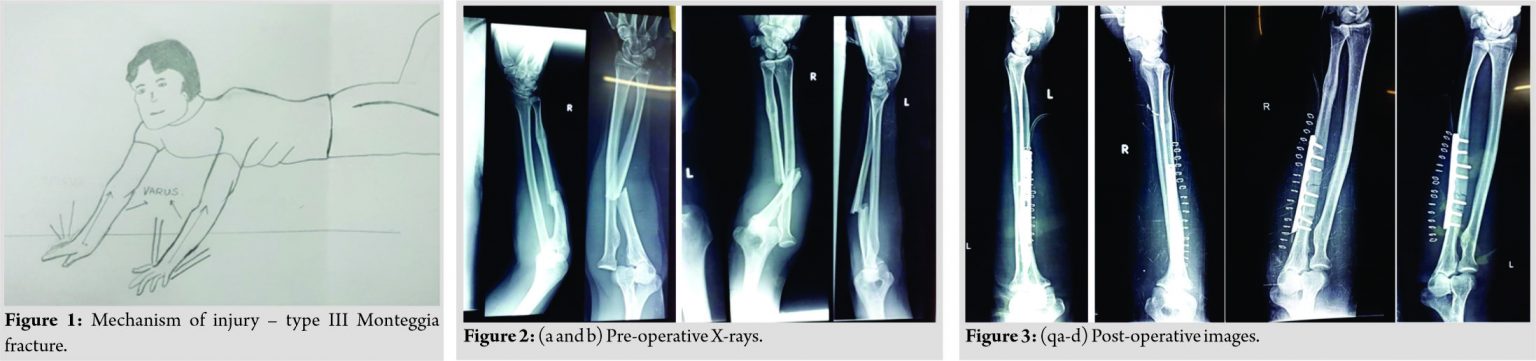

A 35-year-old male came to the emergency with alleged history of roadside accident. The patient was hit from behind from a speeding vehicle and with the impact patient was thrown onto the road with both outstretched hands planted firmly on the ground (to break the impact of fall) with varus stress on both elbows (Fig. 1). This usually produces ulna fracture with tension failure at radial side first and lateral radial head dislocation. There were no external wounds or any distal neurovascular deficit in both upper limbs. There was no history of loss of consciousness or any history of seizures or vomiting and the patient was brought to the emergency department. Here, the patient underwent radiographic imaging of both forearms with elbow with wrist anteroposterior and lateral views. Bilateral above elbow slabs given. X-rays showed proximal 1/3rd ulnar shafts with lateral radial head dislocation (Fig. 2a and b), which accounts for Bado classification typeIII Monteggia fracture bilaterally, which almost exclusively occurs in children, but a rare occurrence in adults as in this case report [3].

Workup for surgery was done and was taken to the OR, where the patient was placed in a supine position, skin preparation and draping was performed for both upper limbs. A posterior skin incision was first performed on the right forearm. An anatomical reduction was achieved, and open reduction and internal fixation of the bilateral ulna were done with posterior anatomical plates and closed repositioning of radial head was done bilaterally. Fluoroscopy was used to confirm appropriate articular reduction, position of the devices, and ulnohumeral joint reduction. The elbow appeared stable through full range of motion and wound closed in layers and suction drain out bilaterally. Postoperatively, bilateral above-elbow pop slabs were given. Post-operative X-rays were performed (Fig 3a, b, c, d). Drains were removed after 48 h; at that time, the patient started passive-assisted exercises and active motion and pop slabs reapplied. Alternate day dressings were done, and skin sutures removed on 21st post-operative day along with the slabs. The patient was advised physiotherapy. X-rays were performed at 1 month of follow-up (Fig. 4) and then again at 5 months of follow-up (Fig. 5) along with clinical pictures after 5 months of follow-up (Fig. 6a, b, c, d, e, f).